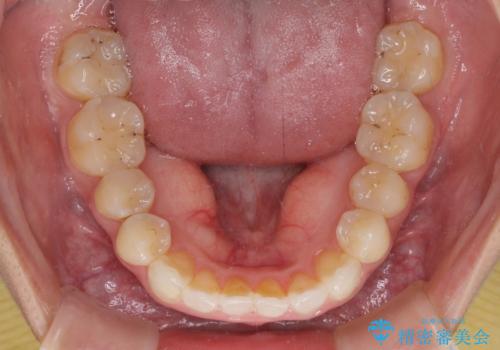

- 中学生の時に矯正治療をしたものの、後戻りを気にして来院された患者様です。

骨格的に下顎が右側に変位しているため、左右の咬み合わせを理想的なものに改善することはできませんが、インビザラインにて歯列を整えることとしました。

骨格的なズレによる左右差は改善できませんでしたが、上下の正中を極力合わせるようにすることができました。